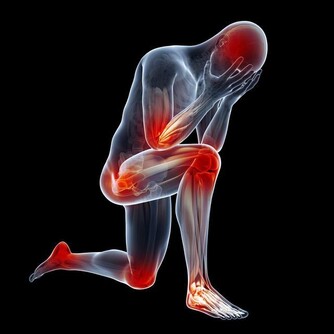

中國有1億靜脈曲張患者,常做3個小動作,幫你遠離靜脈血栓

目前中國有1億人左右患有靜脈曲張,靜脈曲張的問題不僅僅是看上去不雅觀,更重要的是,當靜脈曲張累積到深靜脈時,或引起肺栓塞,導致猝死。

所以我們應該對靜脈曲張保持足夠的警惕,及時干預,防止出現深靜脈血栓,增加猝死的風險。因此,今天,我們主要講講靜脈曲張的預防。

讓我們先來回想一下,靜脈曲張的形成原因主要有哪兩個?一是先天性的血管壁薄弱,這一點我們沒法干預;另外一個原因是久坐久站,姿勢不正確。這個是完全可以改正的。因此,避免靜脈曲張的關鍵就是避免久站久坐。

當你保持站立或者坐立的狀態1小時以上的時候,就應該起身活動一下了,沿著房間慢慢溜達一下,通過小腿的肌肉泵作用,使血液回流;另外,工作了一天,晚上回家躺在床上,我建議大家抬高下肢,這樣也是藉助重力的作用,使下肢的血液回流。